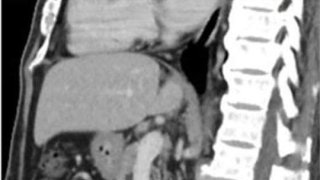

ไต้หวัน 🇹🇼 : 🥥 ชายเมือง เกาสง ลูกมะพร้าวติดในช่องทวาร 🥥โรงพยาบาลแห่งหนึ่งในเมืองเกาสง รับผู้ป่วยชาย ชายวัย 56 ปี เข้าห้องฉุกเฉิน อาการปัสสาวะลำบาก ท้องผูกรุนแรง ปวดท้องมา 2 วันแล้ว ผลตรวจ CT scan พบว่า กระเพาะปัสสาวะบวมเหมือน ลูกฟุตบอล สิ่งที่อุดตัน อยู่ในนั้นคือ ลูกมะพร้าว ขนาดยาว 7.5 ซม. กว้าง 5.7 ซม. ปิดกั้นท่อปัสสาวะ แพทย์พยายามใช้มือเอาออก ไม่สามารถเอาออกมาได้ กระเพาะปัสสาวะขยายตัวเกือบ 2,00.. ดูเพิ่ม